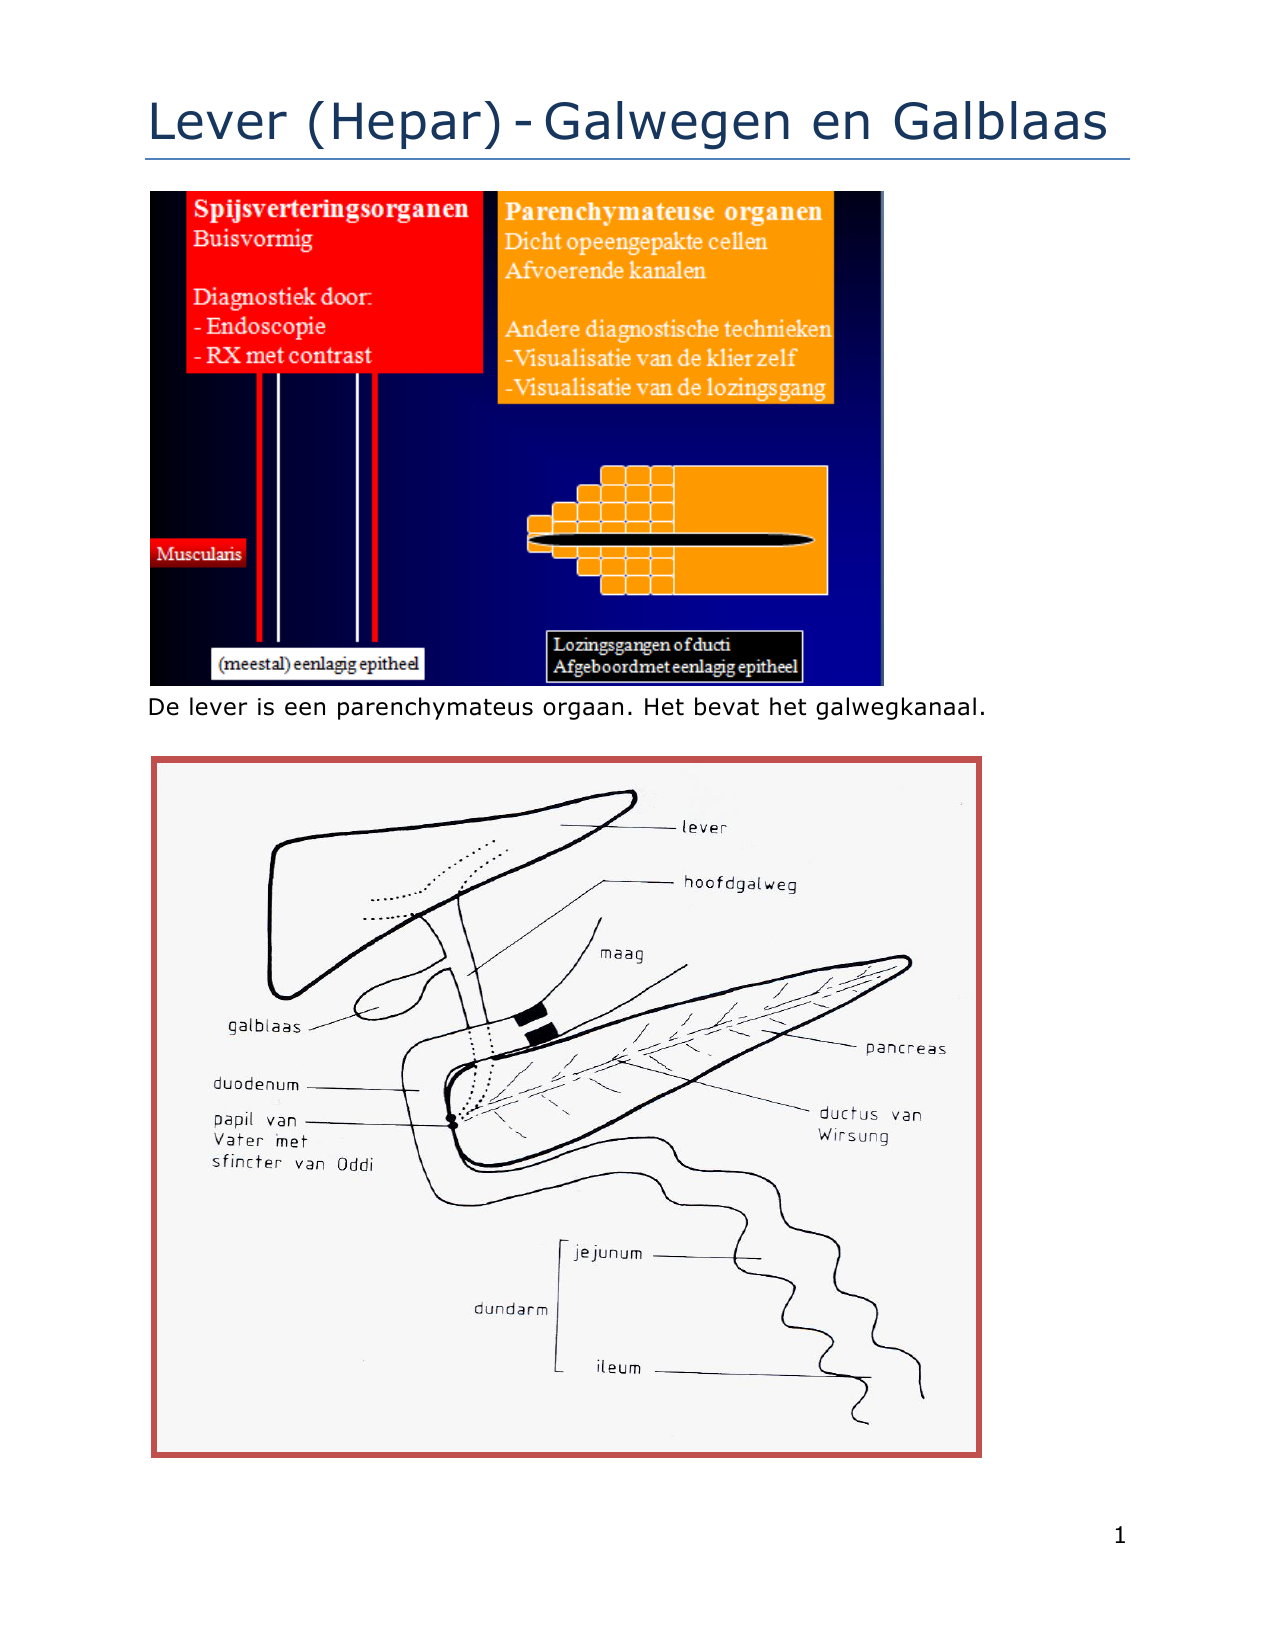

Lever (Hepar)Galwegen en Galblaas

Bij een galwegontsteking (cholangitis) zijn de galwegen in of buiten de lever ontstoken. In de lever zitten veel kleine galkanaaltjes. Deze komen samen in de grotere galwegen. Via de grotere galwegen wordt de galvloeistof afgevoerd naar de galblaas en vervolgens naar de dunne darm. De galblaas.. Auszug. Die extra hepatischen Gallen wege in Form des Gallengangs und der Gallenblase garantieren den großen täglichen Bedarf an fettemulgierender Galle. Jede Unwegsamkeit darin provoziert ein Stenosemuster mit entsprechendem Gallenrückstau, der akut zum tödlichen Leberversagen und chronisch zu einem fibrodestruktiven Reaktionsmuster und.

Lever, galblaas en galwegen Algemene en abdominale heelkunde